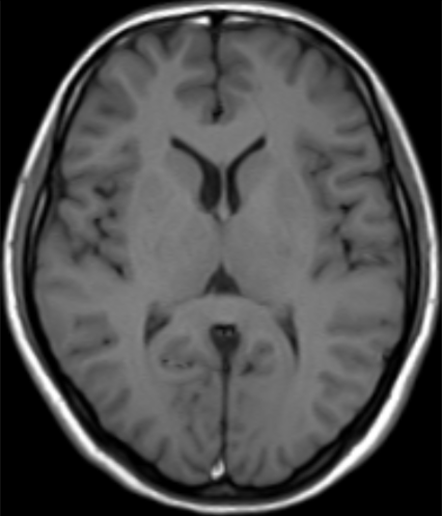

颅脑-T1WI